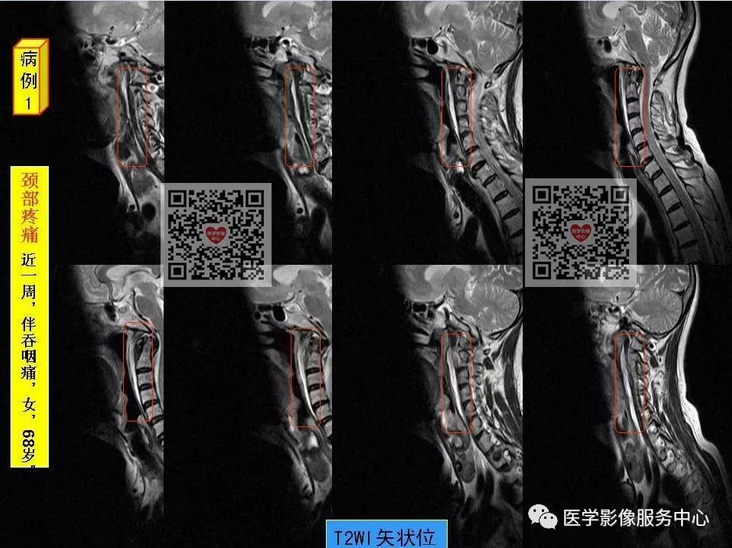

颈椎前缘的条状高信号影,终于知道是什么啦~~

颈项疼痛是临床常见症状,最常见的原因就是颈椎病,包括颈椎骨质增生,颈椎间孔狭窄、颈间盘膨隆突出等表现,综合运用DR、CT、MRI这些影像检查方法,比较容易做出诊断,除此之外,引起颈项疼痛,还有比较少见的原因,不为影像诊断及临床医师所熟知,接下来我们看看下面的2个病例,比较少见的颈长肌肌腱炎。

颈长肌肌腱炎,是以颈项疼痛为主要临床表现的一种疾病,因颈长肌前方毗邻食道及咽部,常常伴发咽部疼痛和吞咽疼痛,临床及影像科医生对其认识较少,常易与其它引起颈项疼痛的疾病混淆 。

其病因为羟磷灰石结晶沉积于颈长肌上斜肌引起的炎性反应,以刺激组织渗出为主。羟磷灰石结晶沉积机制尚不十分明确,可能与损伤、组织坏死和炎症等因素相关。